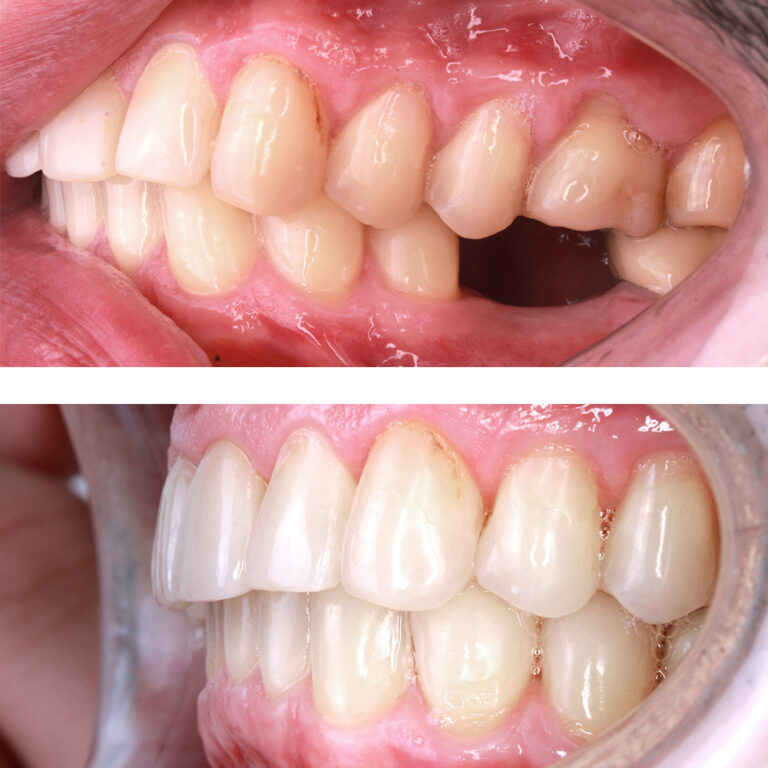

Кейс 12

Бирковская Екатерина Александровна

Количество кап ВЧ 24

Количество кап НЧ 41

ДО

ПОСЛЕ